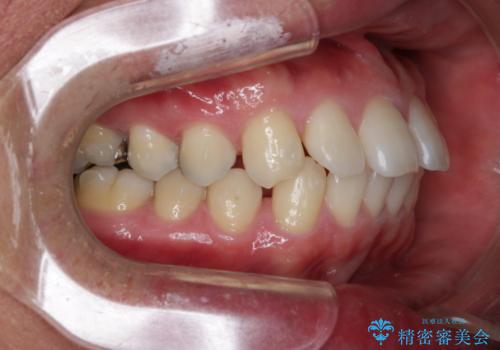

- 全体的に歯と歯の間に隙間があるのが気になるとのことで来院されました。インビザラインでの矯正治療をご希望されました。

隙間については、前歯と奥歯に多数あります。また、上下前歯は、外側に少し倒れているため隙間を閉じつつ、前歯を内側に引っ込めて並べることになりました。